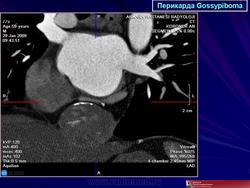

Госсипибома, или текстилома - это название группы осложнений после хирургических вмешательств в результате оставленных в теле пациента инородных предметов. Термин "Госсипибома" состоит из латинского слова gossypium (хлопок) и слова из языка суахили boma (место, где что-то спрятано), по другим данным - греческого "oma" - частицы, обозначающей опухоль. Так или иначе, госсипибома представляет собой матрикс из хлопка, окруженный гранулемой инородного тела. Термин текстилома появился позже и стал использоваться вместо термина "госсипибома", когда в хирургии вместо хлопка начали применять синтетические материалы.

Случай 3: КТ